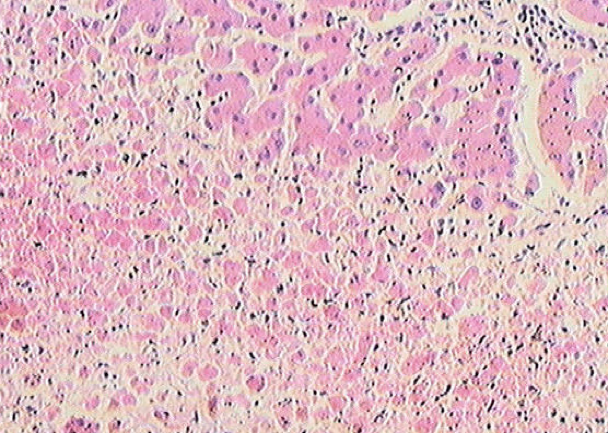

(一)变质—— 损伤

炎症局部组织所发生的变性和坏死称为变质(alteration)。变质既可发生在实质细胞,也可见于间质细胞。例如:病毒性肝炎: